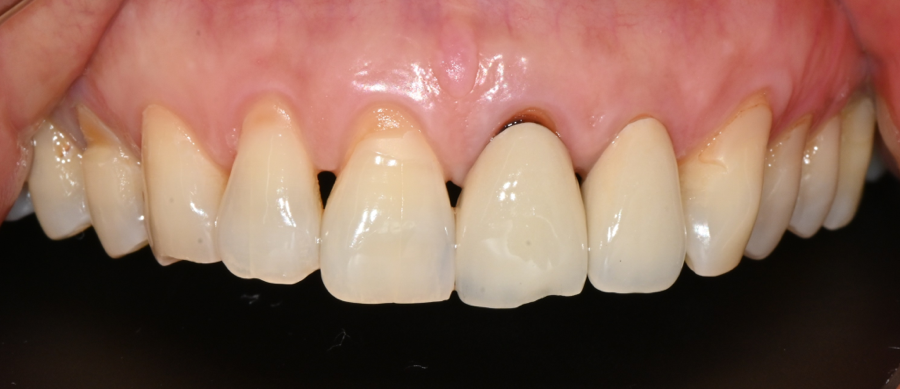

However, in daily life,

• An unstable feeling when using the temporary prosthesis

• Sensitivity when drinking cold water

• A feeling that force was concentrated on a specific area when chewing

kept repeating,

and the patient came in with growing concern about

“whether it was okay to keep using it like this.”